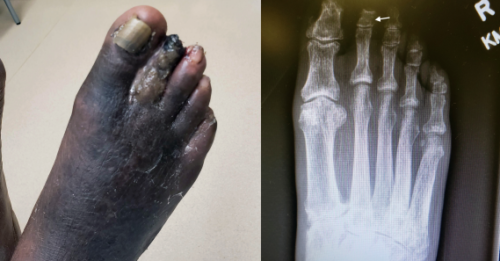

Case Report: Fear of COVID-19 Leads to Gangrene

During the COVID-19 pandemic, there has been a documented decline in emergency department visits for medical and…